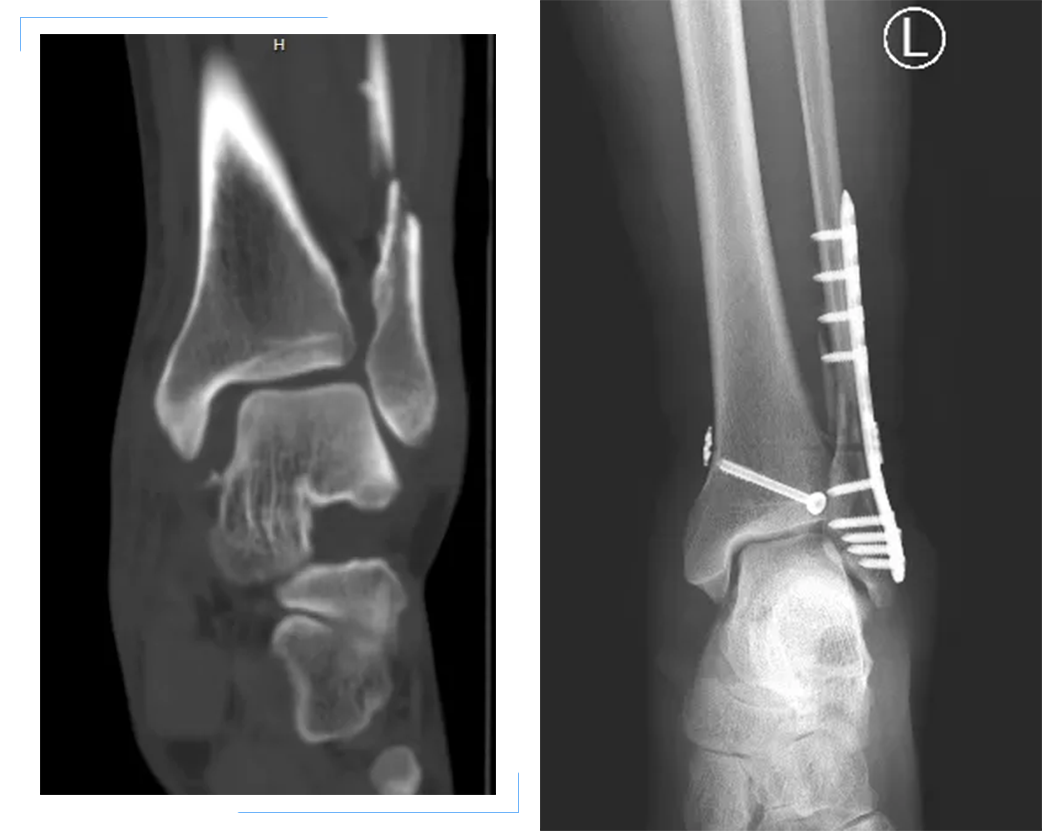

52岁的患者杨某,因下楼时不慎踩空致左踝关节疼痛伴活动受限2小时来院就诊,以左侧踝关节骨折收住创伤骨科,入院经查体、CT检查明确诊断为左侧腓骨骨折、后踝骨折伴踝关节脱位,经过安勇主任医师团队认真研究和充分讨论病情,最终决定为患者行后外侧入路腓骨骨折切开复位钢板内固定+后踝骨折螺钉内固定+踝关节脱位袢钛板内固定手术,手术取得成功。

带袢钢板是一种新型内固定材料,具有“弹性固定”特点,能更好地模拟韧带生理功能,从而提供更稳定的固定效果,此次将带袢钢板应用于下胫腓联合损伤后踝关节脱位的病例,国内各大医院已逐步使用,在我院尚属首例。与传统治疗螺钉内固定的方法相比,使用带袢钢板具有手术操作相对精准、创伤小、恢复快等优点,保留了下胫腓联合的微动功能,更有利于踝关节功能恢复,避免了螺钉松动、断裂及二次手术。